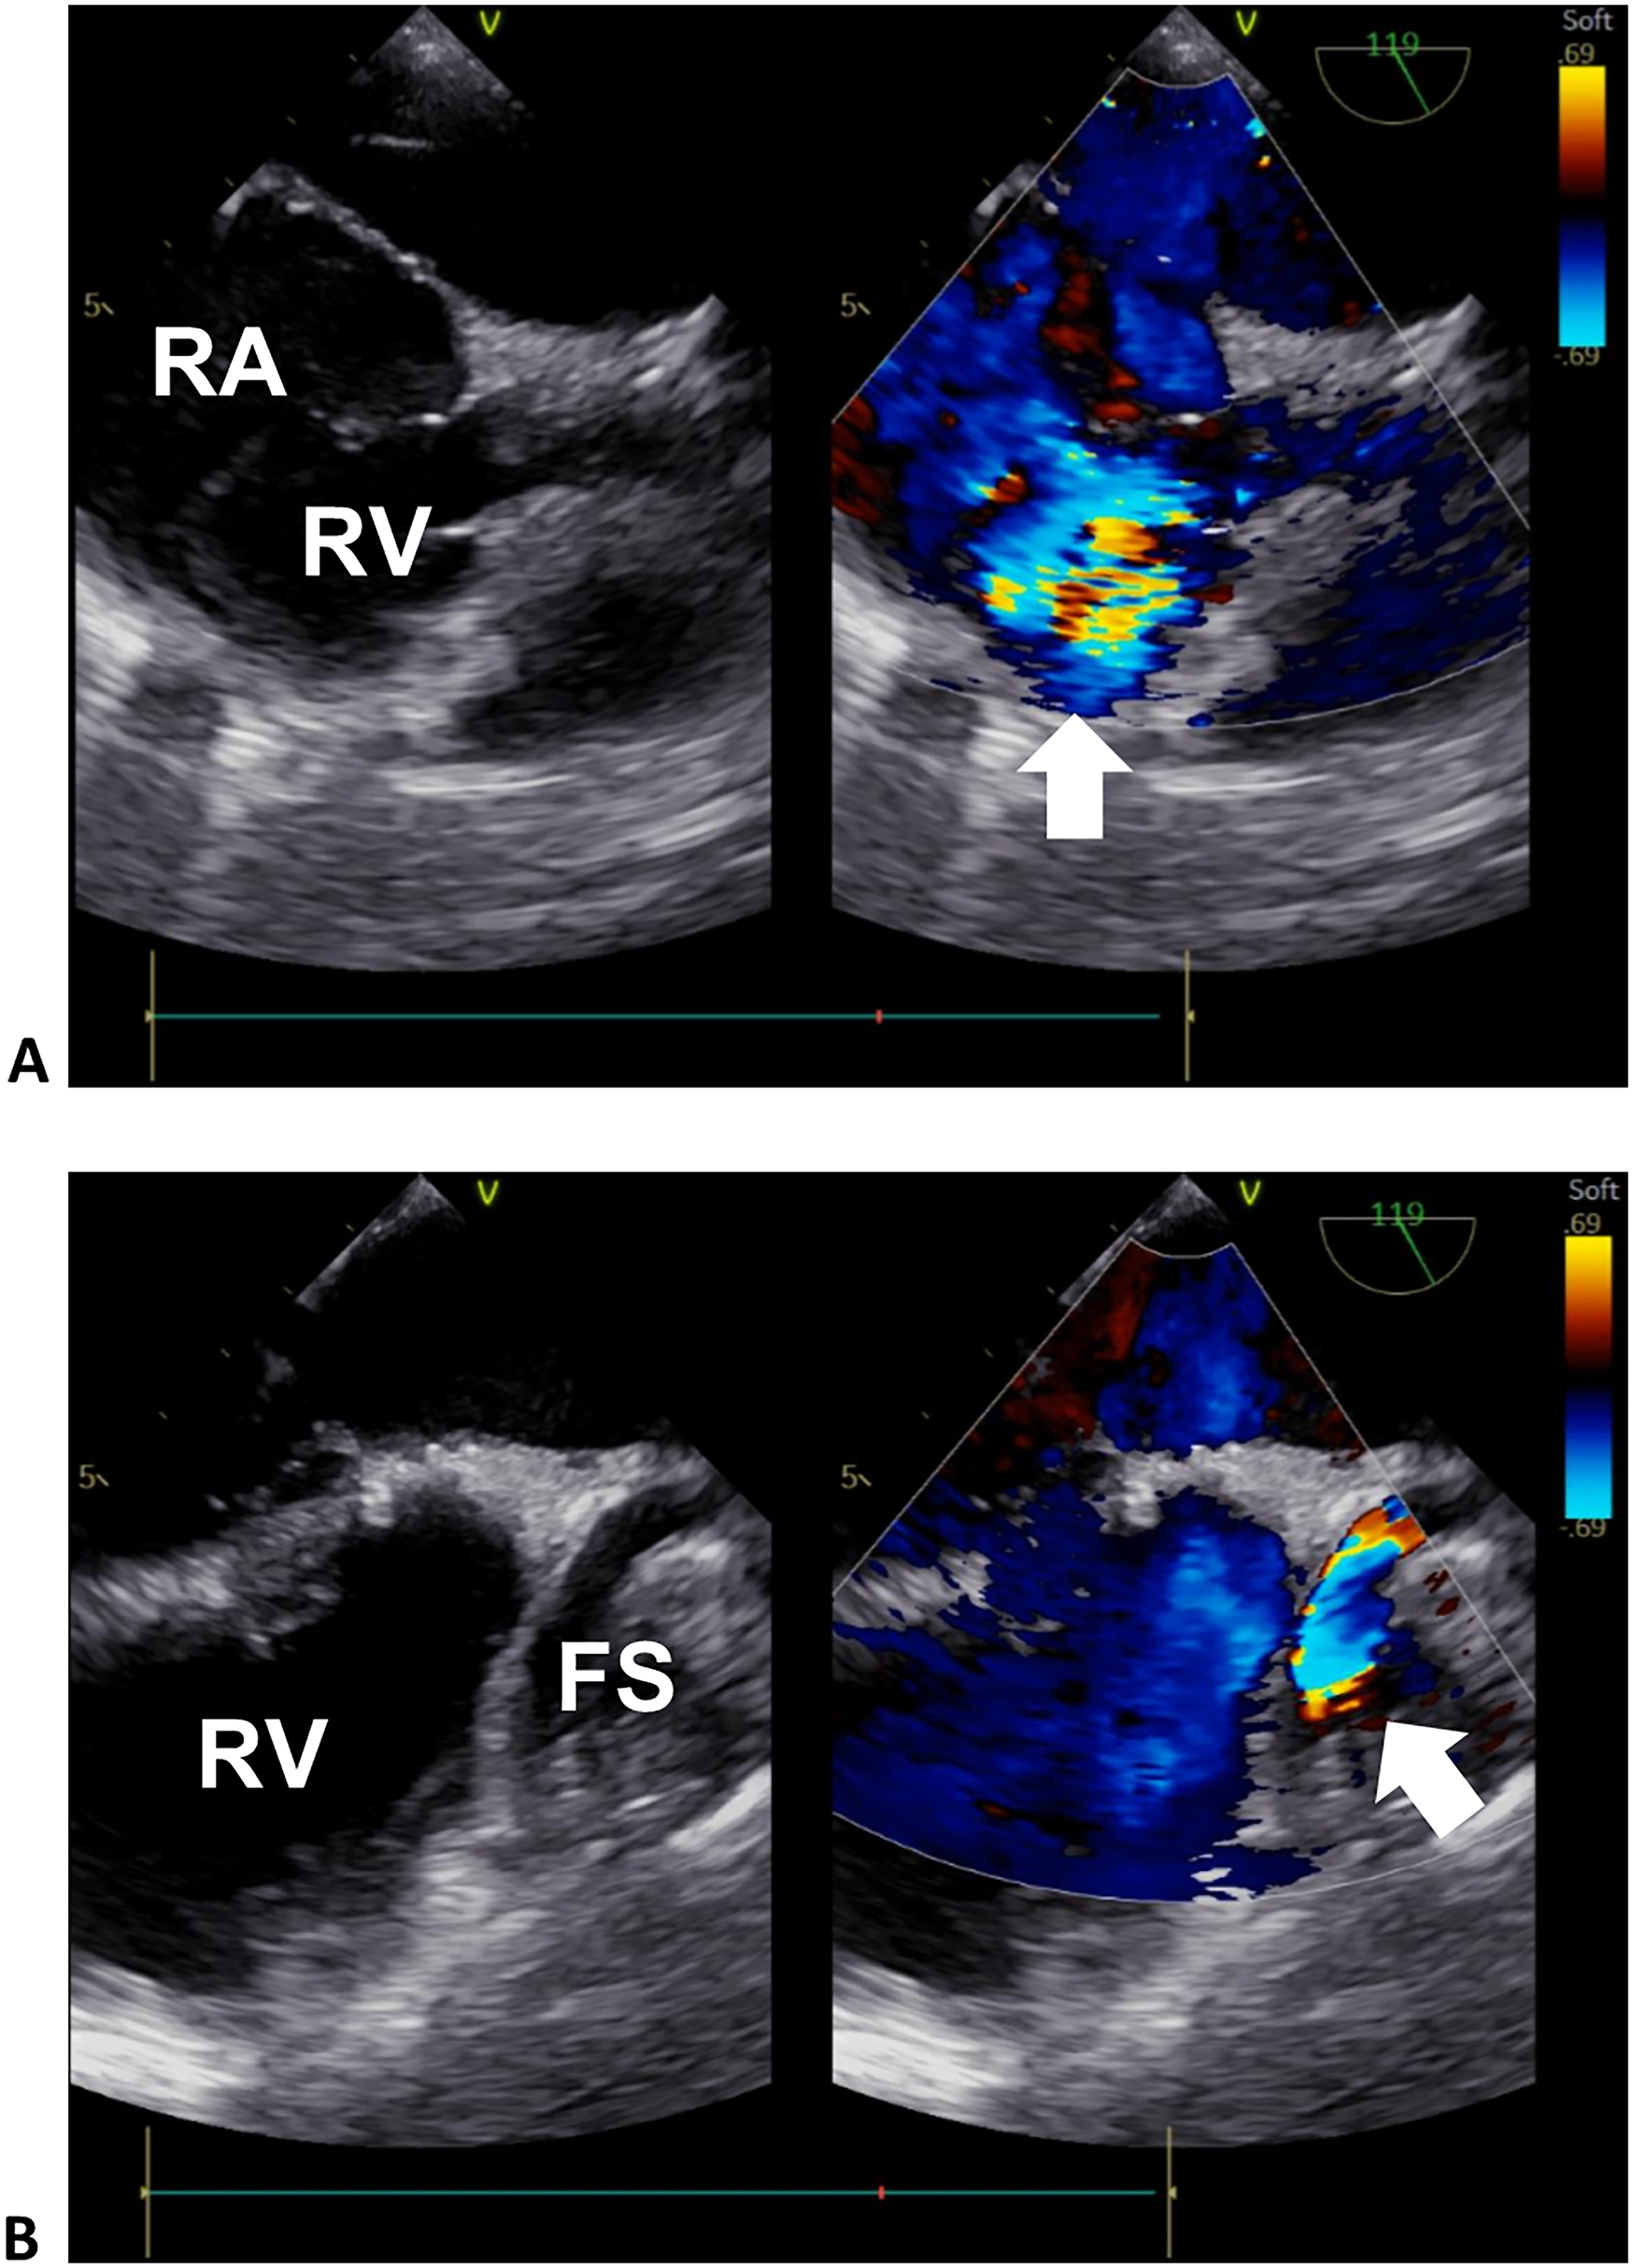

Computed tomography angiography and digital subtraction angiography showed a “dumbbell” RCA ectasia at the origin (ID 14 mm) and the fistula wall in the RA (ID 37mm × 36 mm, forming a fistula sac), and the connecting segment was normal (Figure 1, Supplementary Material Video S1). The ostium from the RCA fistula sac to the RA was 10 mm in width, facing the inferior vena cava. Transesophageal echocardiogram (TEE) showed a continuous flow enhanced during diastole at the entrance (peak velocity 2.5 m/s) and exit (peak velocity 1.8 m/s) of the RCA fistula sac (Figure 2, Supplementary Material Videos S2, S3). Her atria (left ID 44 mm, ref. 27–38 mm; right vertical diameter 62 mm, ref. <53 mm), left ventricle (end of diastole ID 61 mm, ref. 39–52 mm), and pulmonary artery (ID 32 mm, ref. 12–26 mm) were enlarged.

Figure 2

Transesophageal echocardiogram of the right heart. (A) Sectional plane showing the exit flow from the fistula sac into the right heart. (B) Sectional plane showing the entrance flow from the RCA to the fistula sac. The arrows denote the turbulence signals of the exit and entrance flows in (A) and (B), respectively. RA, right atrium; RV, right ventricle; FS, fistula sac.